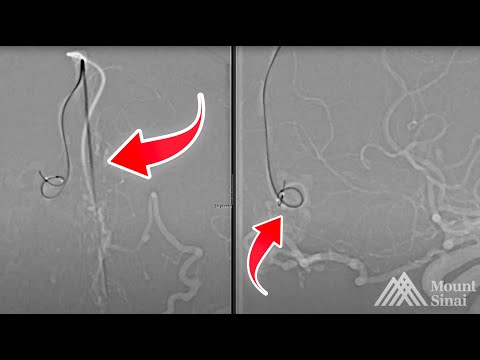

Super Selective Transvenous dAVF Embolization – Maksim Shapiro, M.D.